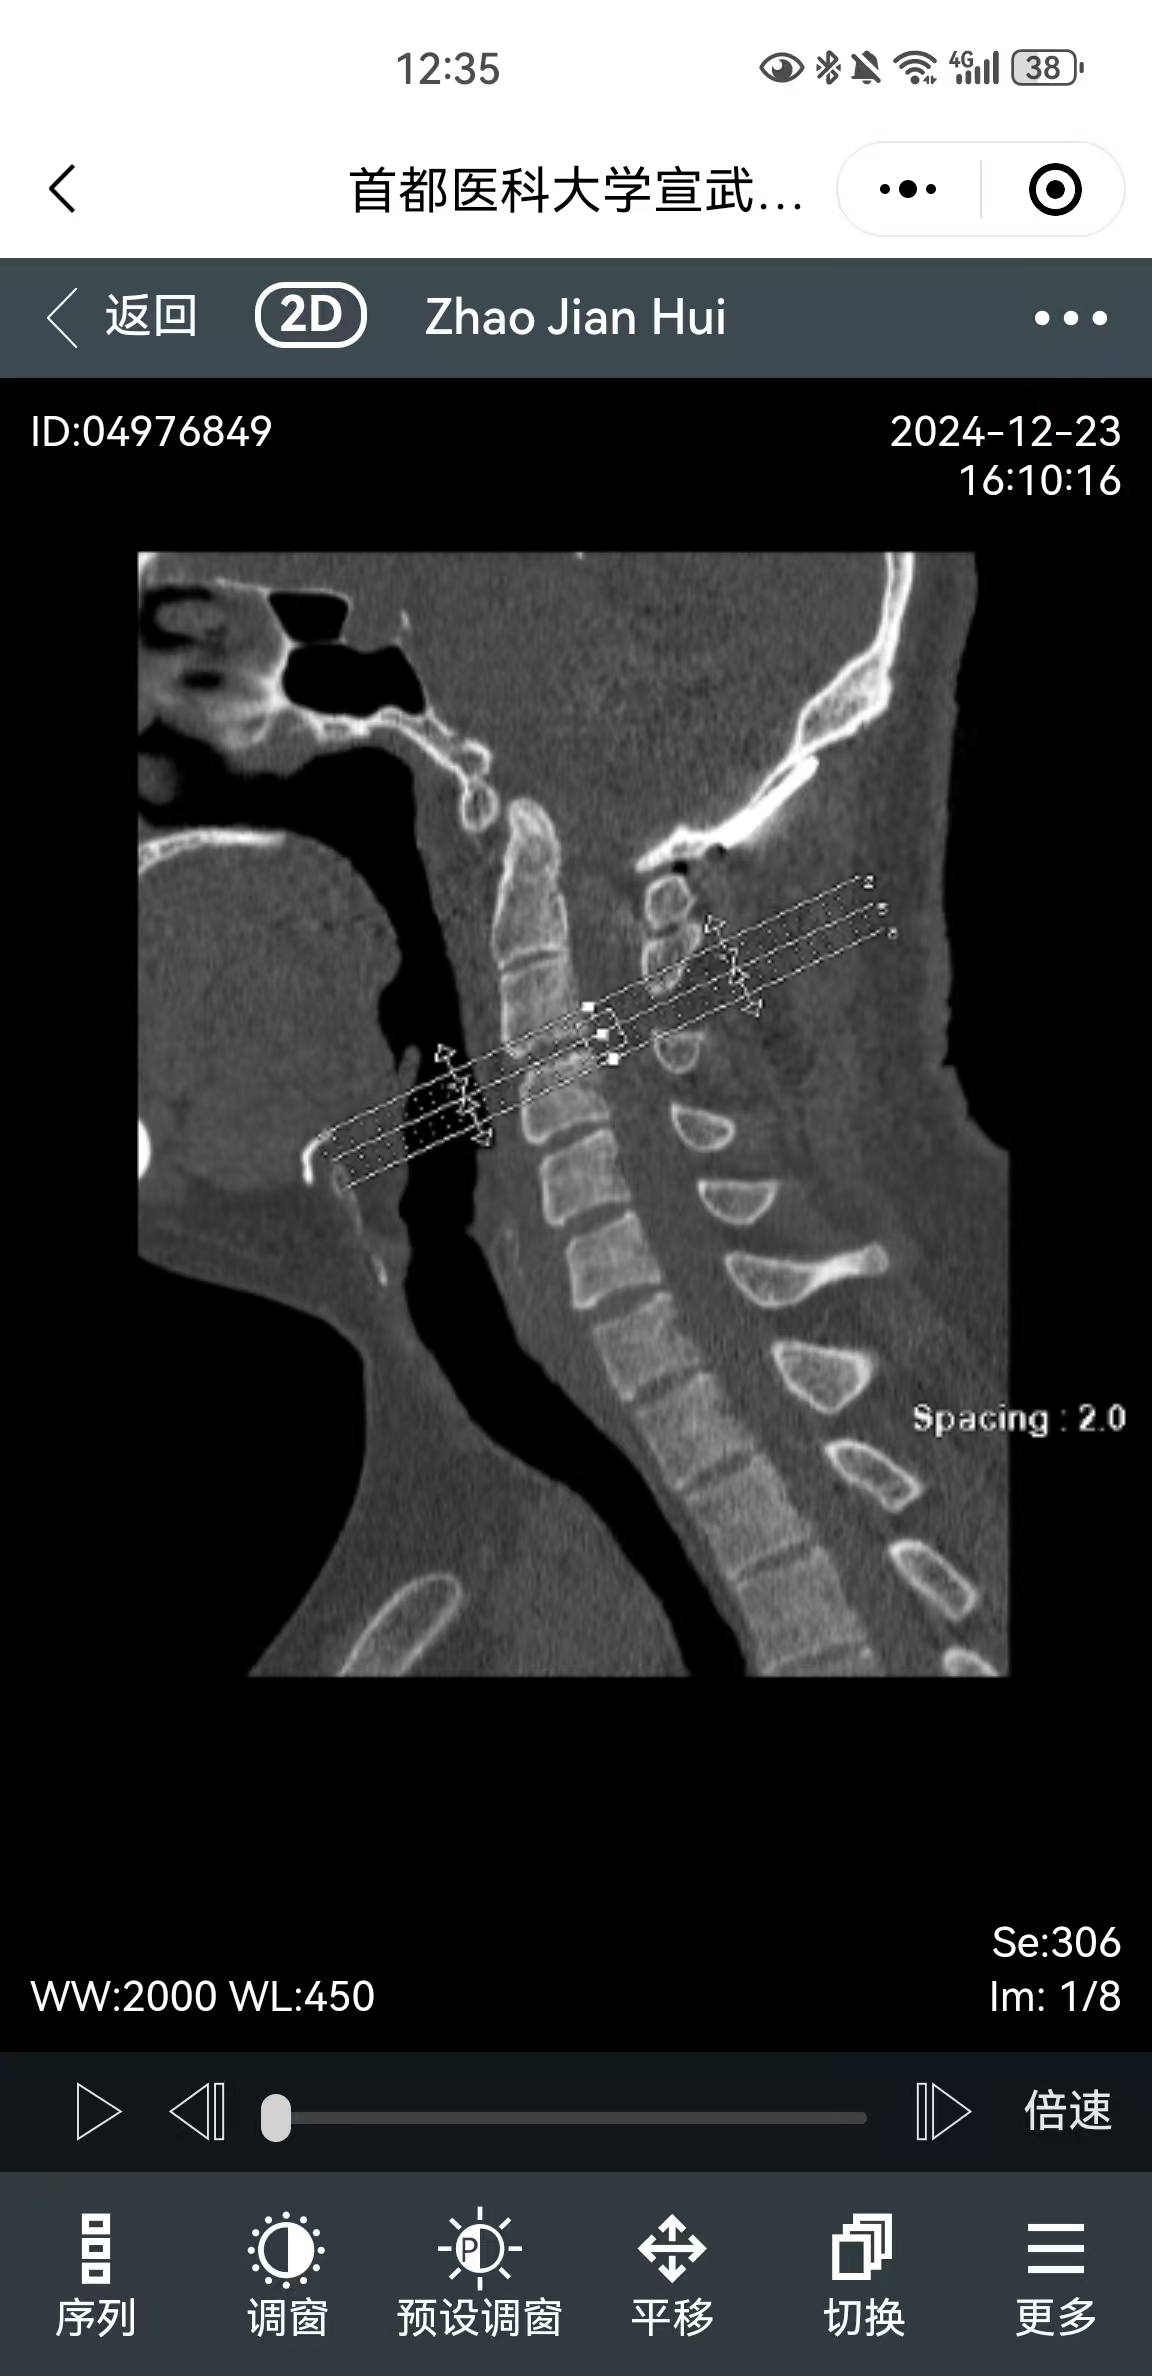

• 术后状况:复位良好,左腿膝盖有没劲缓解了,左手麻木还有

• 术后影像: